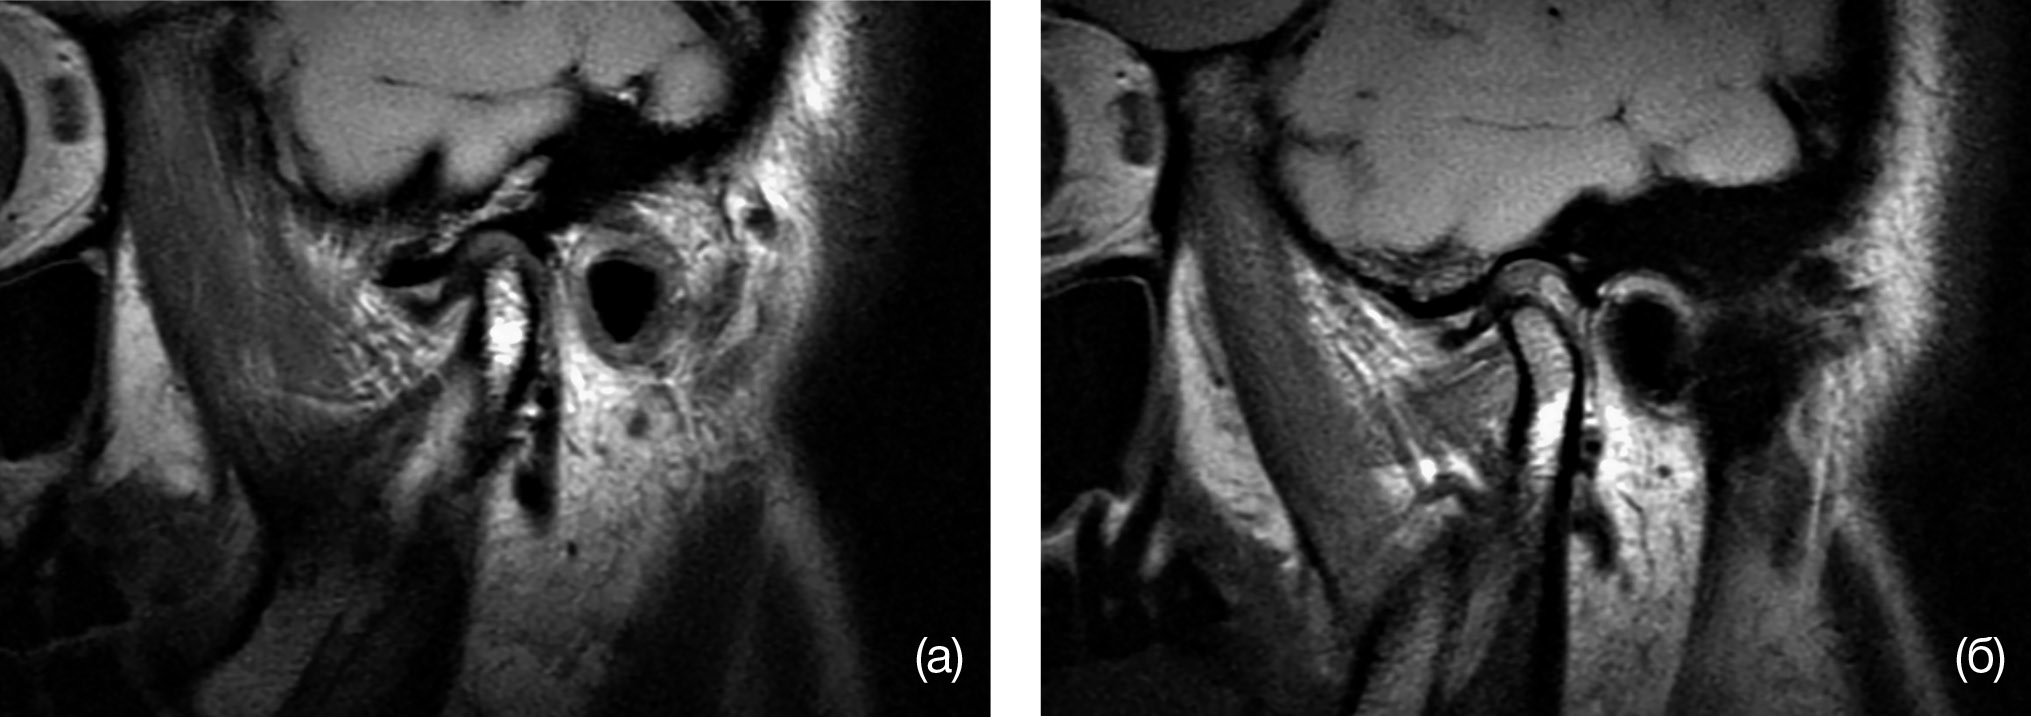

В случае обнаружения функциональных проблем со стороны ВНЧС проводили дополнительные методы обследования, а именно магнитно-резонансную томографию (МРТ) ВНЧС исходно и через 6 мес после лечения в положении открытого и закрытого рта (рис. 1).

Рис. 1. Положение суставной головки при закрытом (а) и открытом (б) рте

Примечание. (а) — передняя дислокация диска височно-нижнечелюстного сустава, (б) — смещение диска височно-нижнечелюстного сустава без репозиции.